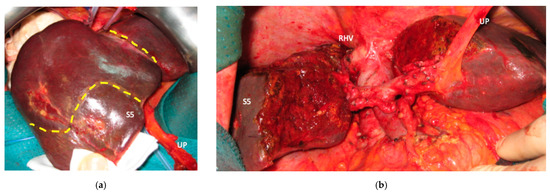

Figure 5. This is a case of liver partition obtained with a major mesohepatectomy performed for CRLM that behaves as biliary cancer infiltrating the confluence of left and right biliary ducts up to S8 duct; this is a highly challenging location for CRLMs at high risk of worsening patient’s quality of life and hampering chemotherapy administration due to jaundice; for this reason, liver resection was performed despite a modest dimensional increase of CRLMs after several courses of FOLFIRI + Bevacizumab administered over three years and after an initial complete radiological response. (a) Intraoperative field with the identification of the two liver transection lines for liver partition (yellow dotted lines). (b) Liver partition at the end of resection of S1/S4/S8 en-bloc with extrahepatic biliary tree resected up to left duct, S5 duct and posterior duct. Three-duct jeujunostomy was performed. Thirty-eight months after liver partition, the patient is under chemotherapy treatment (no jaundice) with stable and asymptomatic extrahepatic and hepatic recurrence. Abbreviations: CRLM: colorectal liver metastases; S: segment; RHV: right hepatic vein; UP: umbilical portion.

Liver partition was obtained with a major mesohepatectomy in two cases with anatomical resection of S1/S4/S8 (en-bloc with biliary tree in one, see Figure 5).

Two out of eight patients with unresectable disease relapse are still alive although with evident disease: one patient 18 months after e-ALPPS performed as a “liver first” strategy for 27 synchronous CRLMs with left colon adenocarcinoma and interaortocaval lymph nodes, then followed by a left hemicolectomy and interaortocaval lymphadenectomy, who experienced an extrahepatic recurrence 3 months after surgery; and one patient 38 months after a major MLP associated with a three-duct jeujunostomy (performed for two CRLMs infiltrating the confluence of left and right bile ducts up to S8 bile duct and with modest dimensional increase of CRLM after 47 cycles of FOLFIRI + Bevacizumab across several reintroductions, Figure 5), with hepatic and extrahepatic recurrence 12 months after surgery.